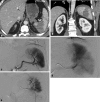

The spleen is the most commonly injured organ after blunt abdominal trauma. Nonoperative management with splenic arterial embolization (SAE) is the current standard of care for hemodynamically stable patients. Current data favor the use of proximal and coil embolization techniques in adults, while observation is suggested in the pediatric population. In this review, the authors describe the most recent evidence informing the clinical indications, techniques, and complications for SAE.